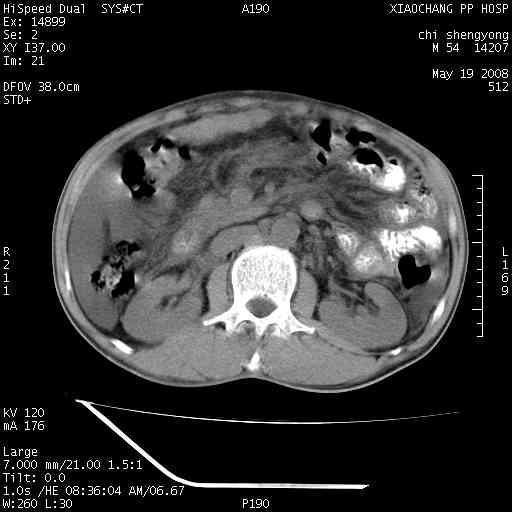

以下是引用zjzjr在2008-5-21 10:52:00的发言:[br]肝左叶巨块型肝癌伴门静脉左支瘤栓形成.肝硬化、腹水,胃底静脉曲张,脾术后改变。

以下是引用随光逐影在2008-5-21 16:20:00的发言:[br]1)肝左叶肝癌伴门静脉左支瘤栓形成,腹膜后淋巴结转移。2)肝硬化、腹水、胃底静脉曲张。3)胆囊炎。4)脾脏缺如,为切除术后所致。